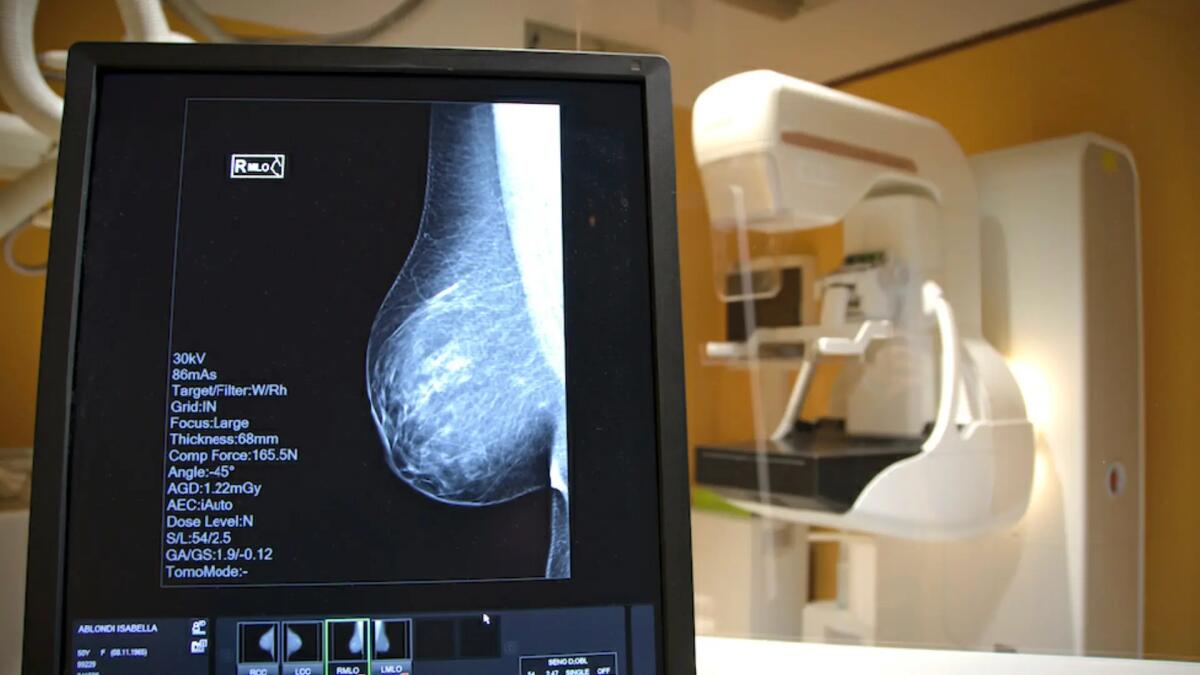

Il 16 marzo 2023 l’Unità Senologica dell’Ospedale di Udine ha ricevuto la conferma della certificazione EUSOMA (European Society of Breast Cancer Specialists) come centro europeo di eccellenza per il trattamento del cancro mammario.

L’Unità Senologica del Santa Maria della Misericordia è in attività da anni: la sua costituzione è stata resa ufficiale con un decreto del Direttore Generale nel marzo del 2021 e nel maggio dello stesso anno è stata ottenuta la prima certificazione, confermata nel 2022 e poi lo scorso 16 marzo. Nel solo 2022 ha trattato 360 nuovi casi di tumore con un totale di 648 interventi chirurgici.

Il tumore della mammella è la neoplasia più frequente nelle donne, in Italia ci sono oltre 50.000 casi all’anno di cui circa 1200 in Friuli Venezia Giulia. Negli ultimi anni, nonostante l’aumento dell’incidenza, il tasso di mortalità continua lentamente a scendere; la diagnosi sempre più precoce grazie ai programmi di screening e a strumenti diagnostici sempre più sofisticati insieme alle terapie sempre più efficaci e mirate hanno migliorato in modo significativo la prognosi.